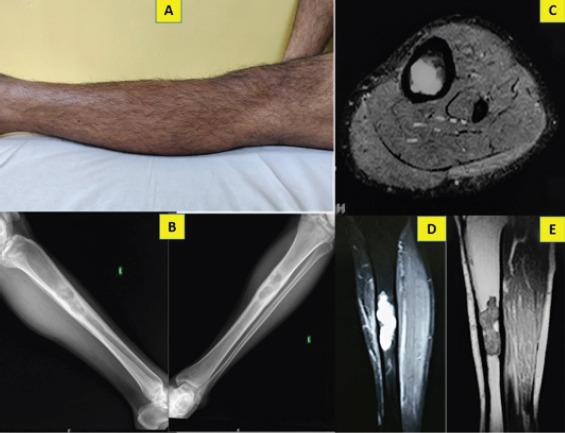

We report the case of a 31-year-old farmer who presented with long standing inconspicuous pain in his left leg which turned out to be a diaphyseal enchondroma even though it demonstrated aggressive radiological features mimicking a chondrosarcoma. Incisional biopsy was done from the scalloped areas to obtain the correct histological diagnosis. He underwent thorough curettage of the lesion and remains asymptomatic 2 years after the procedure. We attempt to discuss the differentials which the orthopedic surgeon should keep in mind for diaphyseal lesions mimicking enchondroma.

Though classically found in metaphysis, Enchondromas are not uncommon in diaphysis of long bones. Enchondromas are generally benign, but can cause diagnostic dilemma when they present with aggressive features at rare locations and surgeons should be wary of the differentials. Despite a size of more than 6 cm and evidence of cortical erosion and intramedullary widening, the lesion could still be benign. Early biopsy will help to differentiate Enchondroma from a malignant transformation or malignant tumor.

我们报告一例31岁农民的病例,他左腿长期存在不明显的疼痛,结果发现是骨干内生软骨瘤,尽管其放射学表现具有侵袭性,类似软骨肉瘤。从扇贝样区域进行了切开活检以获得正确的组织学诊断。他接受了病变的彻底刮除术,术后2年仍无症状。我们试图讨论骨科医生对于模仿内生软骨瘤的骨干病变应牢记的鉴别诊断。

尽管内生软骨瘤经典地见于干骺端,但在长骨骨干中也并不罕见。内生软骨瘤一般为良性,但当它们在罕见部位表现出侵袭性特征时会导致诊断困境,外科医生应警惕鉴别诊断。尽管病变大小超过6cm且有皮质侵蚀和髓内增宽的证据,但该病变仍可能是良性的。早期活检有助于将内生软骨瘤与恶性转化或恶性肿瘤区分开来。